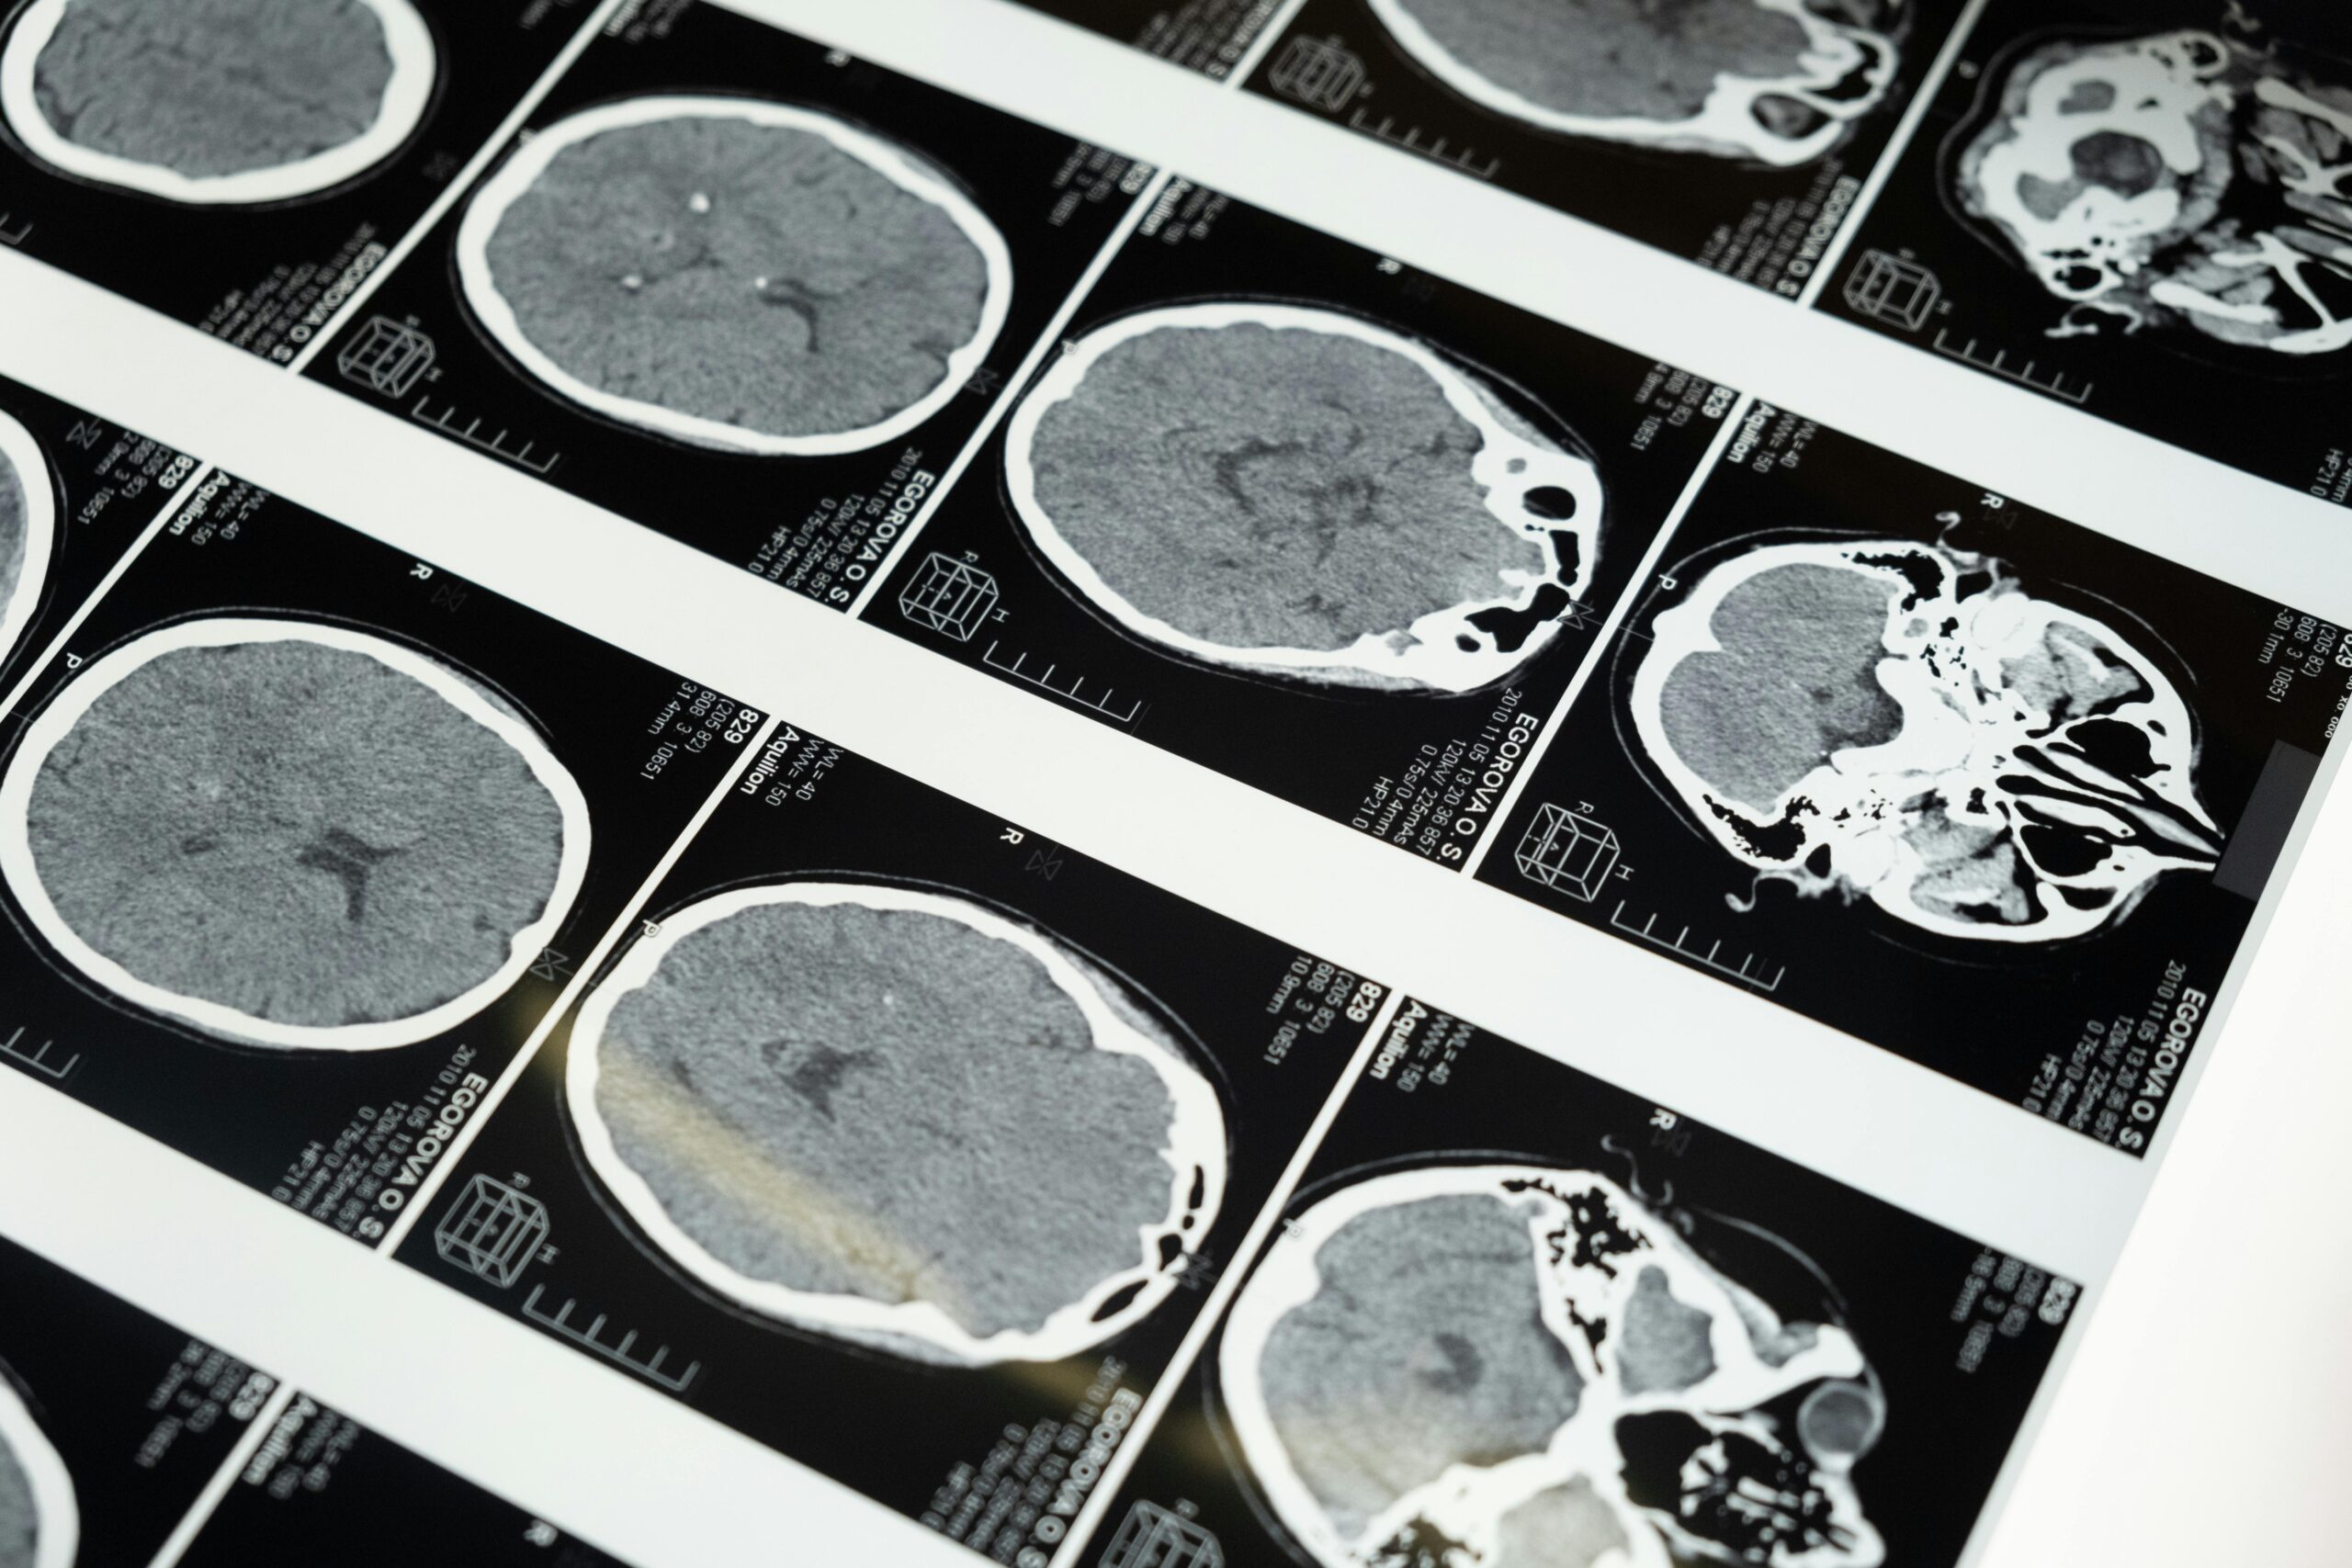

The magazine reported, “New research reveals that soaring heat can overwhelm the brain’s delicate balance, leading to a surge in seizure activity and neurological emergencies.”

The CDC writes, “Heat stroke is the most serious heat-related illness. It occurs when the body can no longer control its temperature: the body’s temperature rises rapidly, the sweating mechanism fails, and the body is unable to cool down. When heat stroke occurs, the body temperature can rise to 106°F or higher within 10 to 15 minutes.” It can cause people to become unconscious or confused.